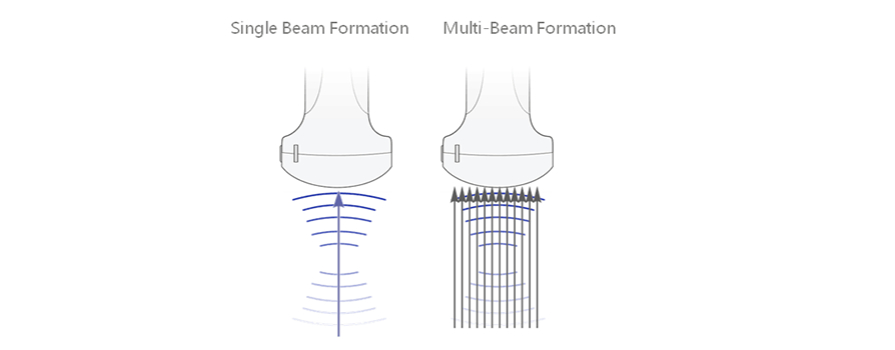

Multistrahlformung

Maximal 12-maliges Tasking pro ├╝bertragenem Strahl, was zu einer hervorragenden zeitlichen Aufl?sung und einer h?heren Bildrate f├╝hrt.